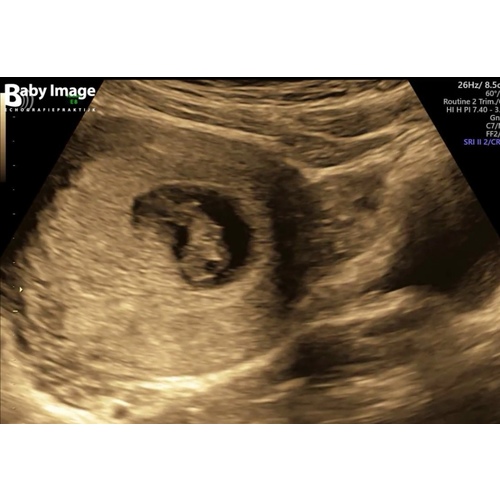

Dit is de mijne 馃槈

Ook jongen xxx Kim